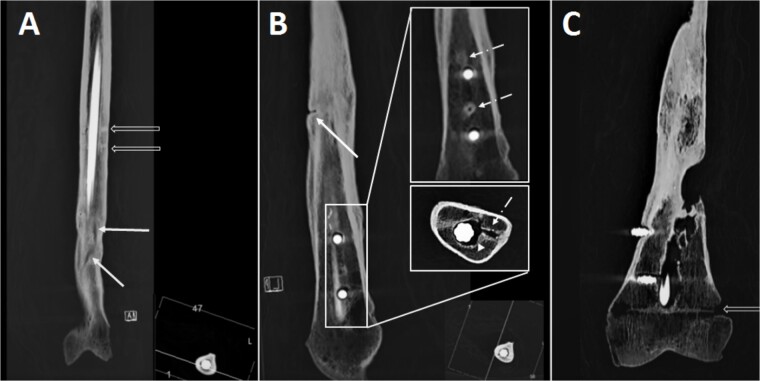

识别身份不明的遗骸涉及使用生物识别资料对死前和死后特征进行比较。国际刑事警察组织(国际刑警组织)将人类学鉴定资料称为二级鉴定资料,往往被认为不如 DNA、指纹和牙科记录(称为一级鉴定资料)可靠。然而,在许多情况下,人类学识别资料已被证明与主要资料来源一样具有鉴别力,并在正面识别中发挥着决定性作用。为了保证更好地利用人类学鉴定资料,不仅有必要制定标准协议和统计框架,而且有必要在日常实践中测试不同的鉴定方法。在鉴定过程中,骨骼的死前创伤证据是一种宝贵的辅助手段,尤其是在确定了造成伤害的创伤事件的确切类型的情况下。在这里,我们介绍了一个案例,在该案例中,人类学分析和成像相结合,证实了不完整遗骸中有趣而独特的死前创伤事件序列。据推测,这具遗骸属于几年前失踪的一个人,其医疗记录显示其右股骨有独特的外伤史。此人曾因从高处坠落而造成骨折,在原发性外伤发生 10 年后,又因枪伤而造成同一骨骼骨折;两处骨折均接受了髓内钉固定治疗。虽然人类学分析与失踪者的生物特征相符,并确定右股骨上的愈合缺损与枪伤相符,但放射学检查显示,该骨头在不同场合接受过三次手术。放射检查还发现,枪伤缺损处附近有一处已经愈合的骨折。除了介绍这个具体案例的鉴定过程外,本文还讨论了尸体创伤鉴定的困难、结合宏观和放射学分析帮助重建先前创伤事件的重要性,以及在法医鉴定中发挥重要作用的愈合骨折的损伤机制。

Identification of unidentified remains involves a comparison of ante- and postmortem features using biological identifiers. Anthropological identifiers, referred to by International Criminal Police Organization (INTERPOL) as secondary identifiers, have often been judged less reliable than DNA, fingerprints and dental records (referred to as primary identifiers). However, anthropological identifiers have been proven as discriminatory as the primary sources in many instances, and play a decisive role in positive identification. To guarantee better use of anthropological identifiers, it is not only essential to develop standard protocols and statistical frameworks, but also to test different identification approaches in cases from daily practice. Evidence of skeletal antemortem trauma can be a valuable aid in the identification process, especially if the exact type of traumatic event causing the injury is identified. Here, we present a case in which the combination of anthropological analysis and imaging confirmed an interesting and unique sequence of antemortem traumatic events in incomplete skeletal remains. The remains were assumed to pertain to an individual who went missing several years earlier, and whose medical records revealed a unique history of trauma to the right femur. The individual had sustained a fracture due to a fall from a high height followed, 10 years after the primary trauma, by a gunshot wound to the same bone; both treated by intramedullary nail fixation. While the anthropological analysis matched the biological profile of the missing individual and identified a healed defect to the right femur compatible with a gunshot wound, the radiological examination indicated that the bone underwent three surgical procedures on different occasions. Radiological examination also identified a pre-existing healed fracture adjacent to the gunshot defect. In addition to presenting the identification process in this specific case, this article discusses the difficulties in antemortem trauma interpretation, importance of combining macroscopic and radiological analysis to aid the reconstruction of previous traumatic events and mechanisms of injury from healed fractures that can play important roles in forensic human identification.